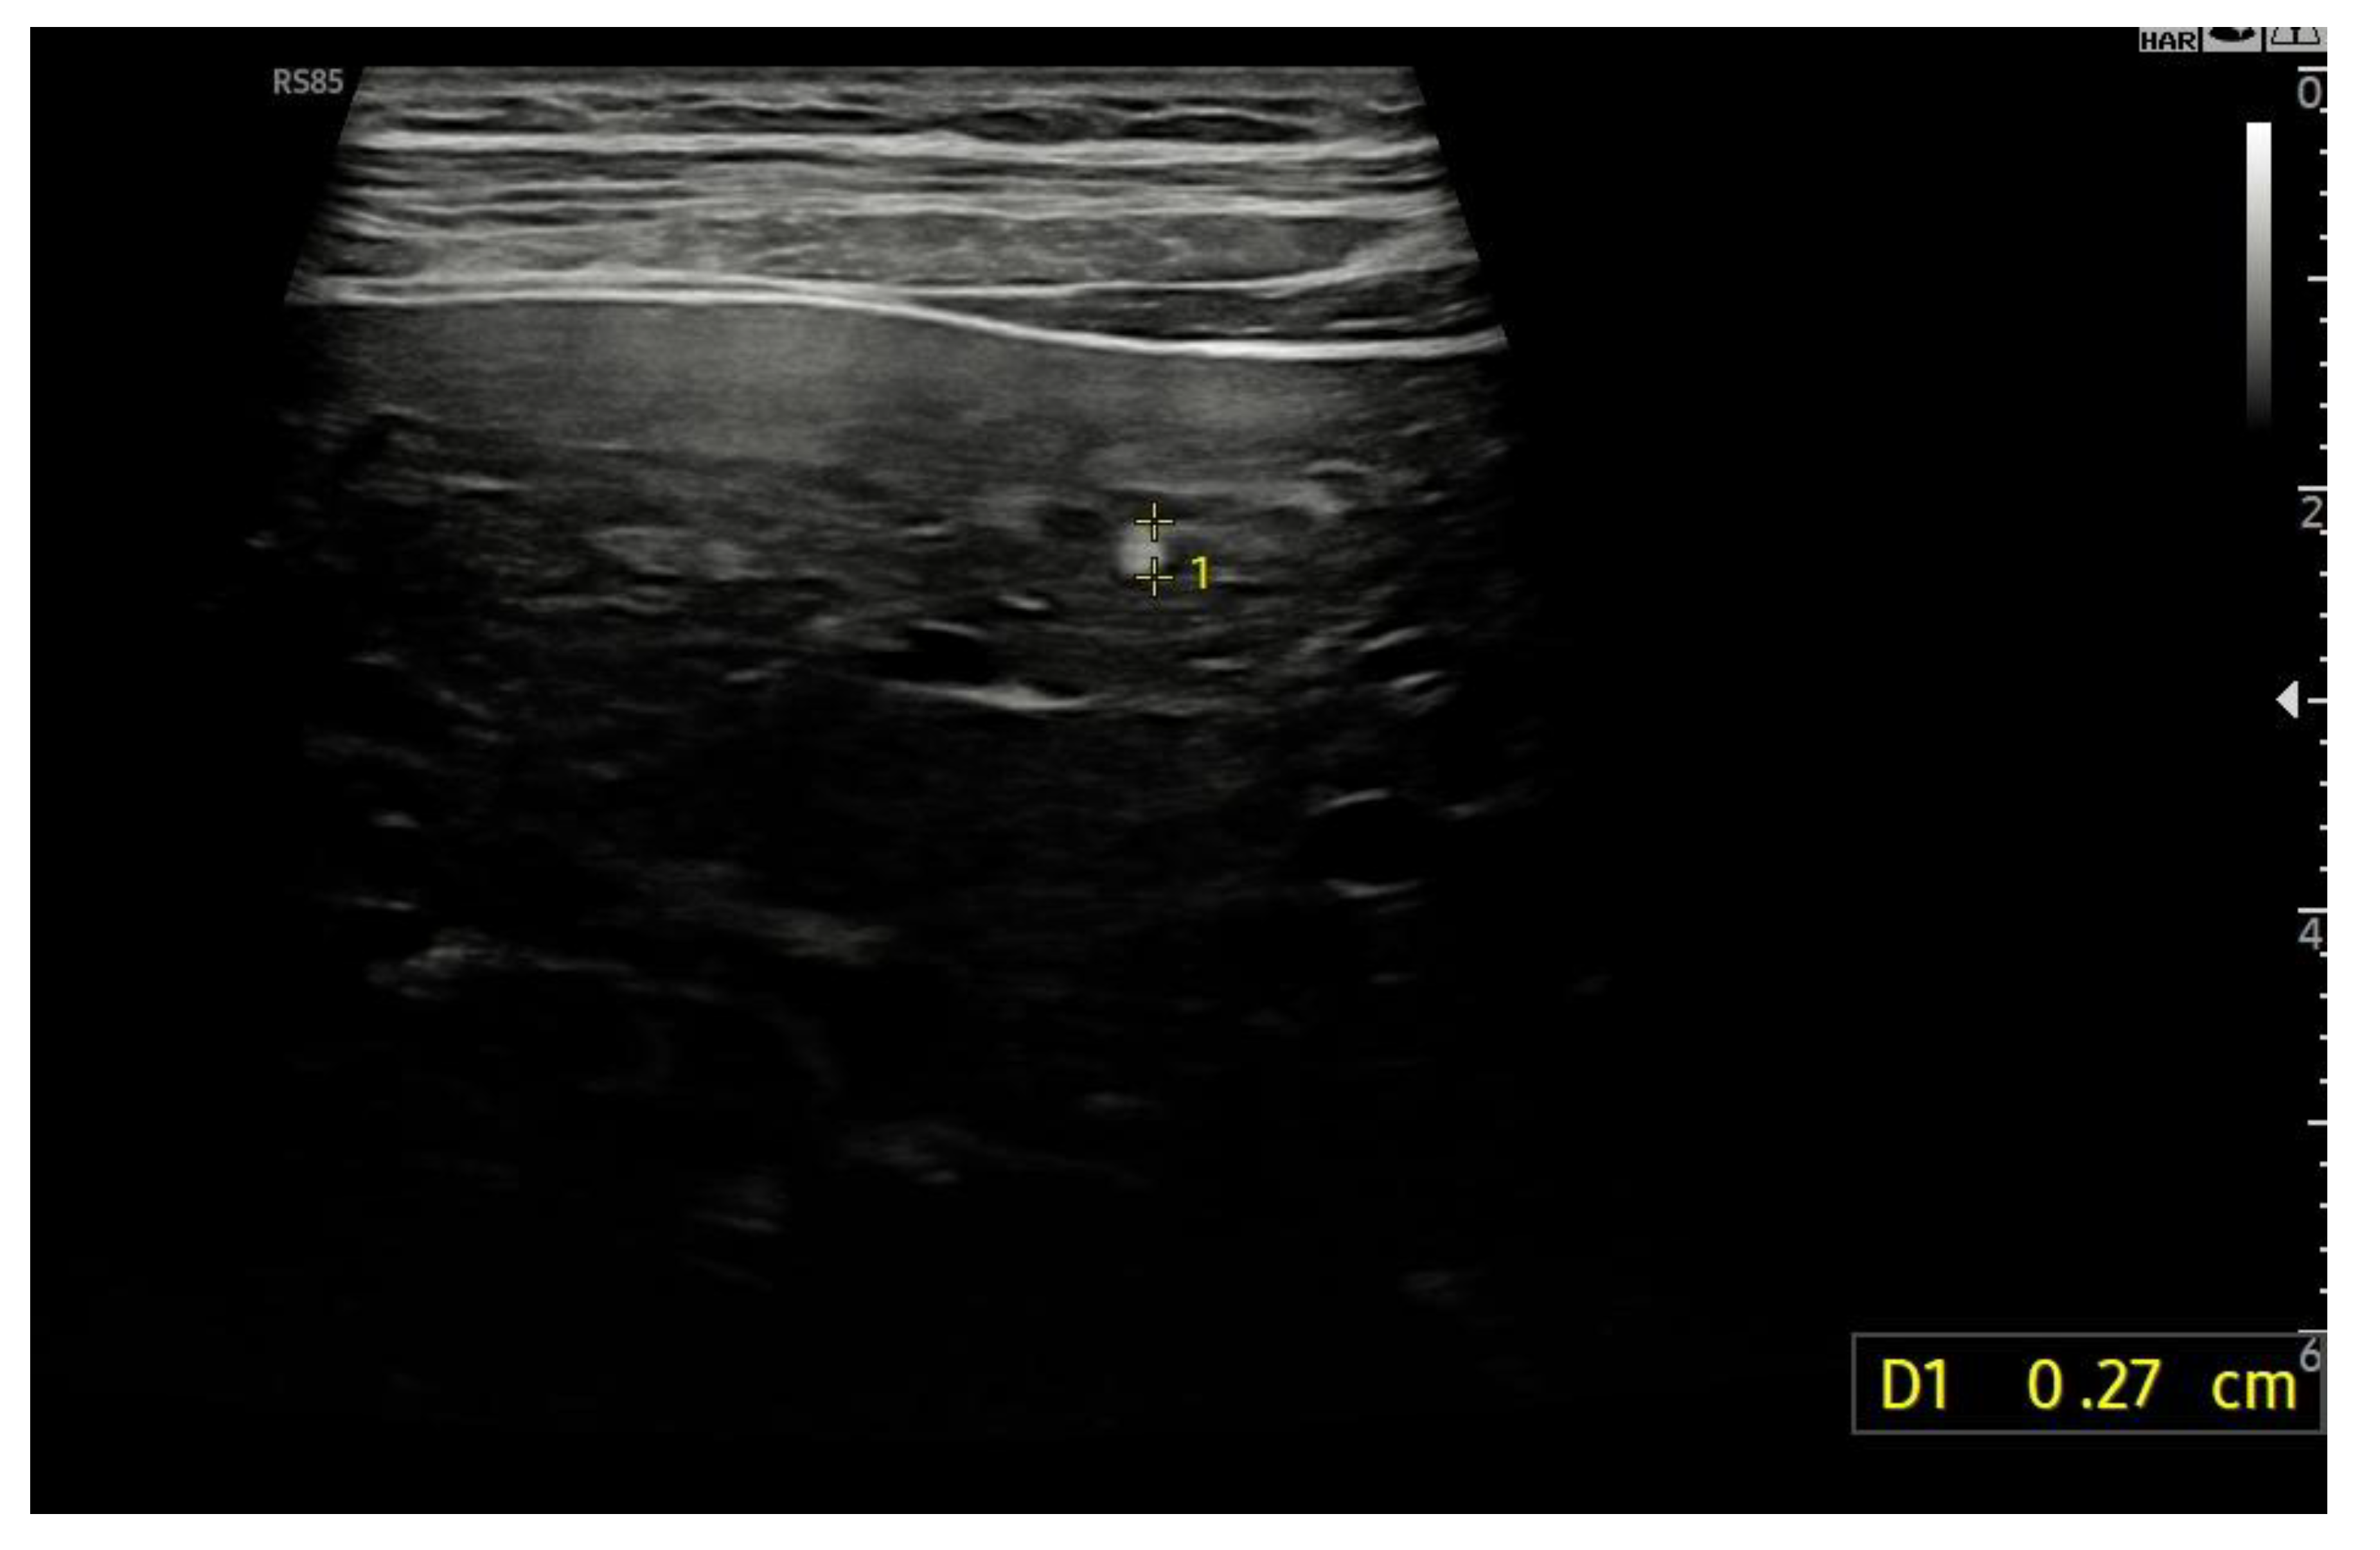

8.1. Ultrasound Differentiation of Liver Nodules

| Ultrasound | B-mode | Small, hyperechoic, sometimes multiple lesions | HCC may be iso- or hypoechoic, larger, with irregular margins |